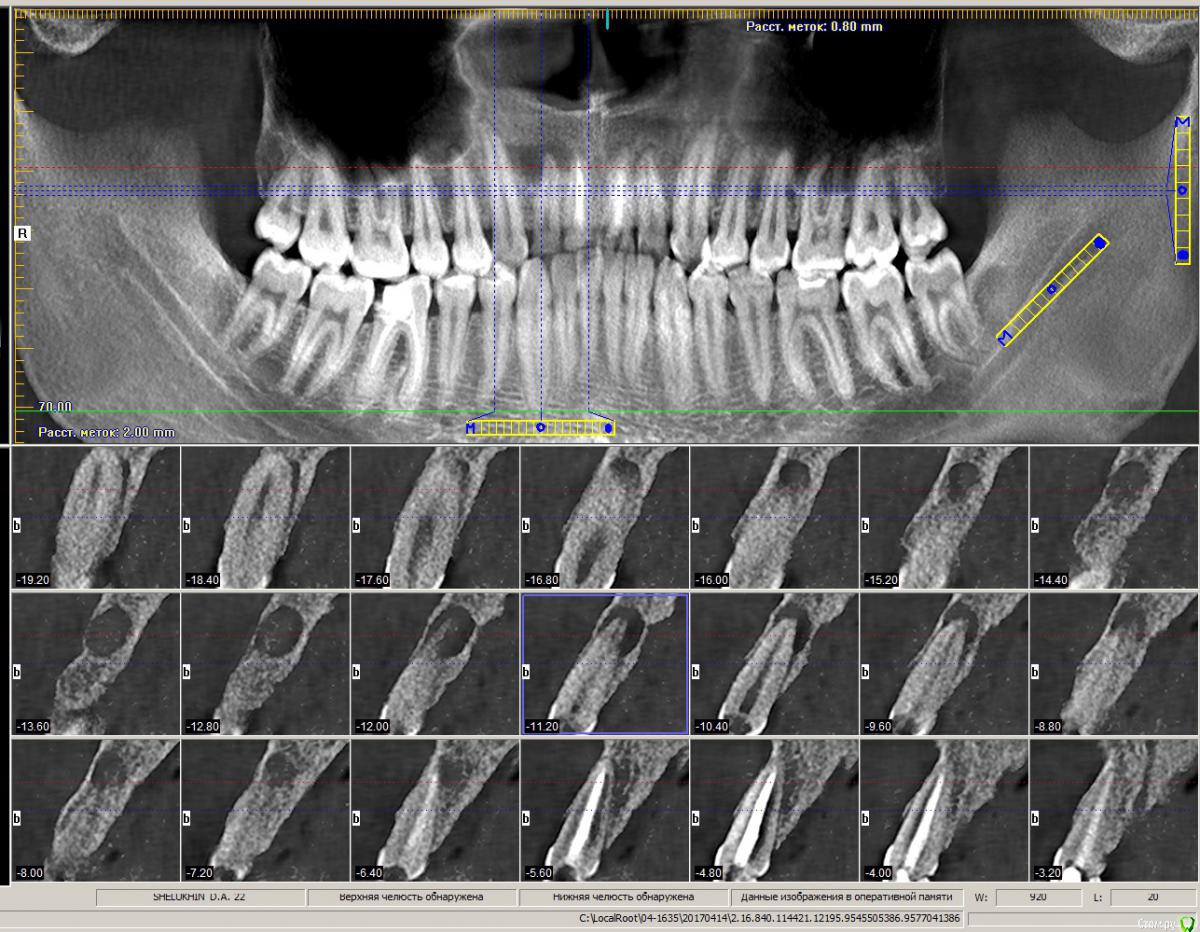

Shelly2000 Опубликовано 22 апреля, 2017 Поделиться Опубликовано 22 апреля, 2017 Здравствуйте! Сыну 22 года, но с лечением зубов уже сталкивался неоднократно. Пару недель назад отвалилась существенная часть коронки второго правого резца. Сделали КТ, посетили несколько клиник. Мнения разных стоматологов совпали только в одном - есть киста, и её можно попробовать лечить. Дальше пошли сильные расхождения в методике, сроках и вероятности достижения положительного результата. Где-то считают, что лечебный препарат (каласепт) нужно закладывать в этот зуб дважды, с промежутком в 10-14 дней, а после этого пломбировать канал. Где-то называют сроки в 1-2 месяца и уверяют, что для правильного лечения необходимо вскрывать соседний запломбированный 11-й зуб и закладывать лекарство и через него тоже (при этом именно плохое пломбирование 11-го зуба считают самой вероятной причиной образования кисты). Самая длительная версия - полгода-год, с регулярной ежемесячной сменой лекарства в больном зубе, причём сразу предупредили, что после первой закладки десна может опухнуть, так как этим перекроется путь выхода нагноений, которые сейчас через зуб малыми количествами незаметно выходят. В случае, если такое лечение не даст положительного результата, была описана хирургическая процедура механического удаления кисты через разрез с нёбной стороны.При всех описанных манипуляциях нигде не давали гарантию, что зуб удастся спасти, а в одной клинике даже сразу просчитали стоимость установки имплантата, но опять же - только после того, как ситуация с костной тканью нормализуется.Хотелось бы понять, сколько реально может занять лечение, так как до его завершения невозможно заниматься протезированием коронки на этот и соседний зуб. Какой из вариантов лечения правильный?Сделал скрины из КТ. Если не смутит объём полного исследования - вот ссылки на версию в iCATVision: https://yadi.sk/d/-kkaw4FG3HEGA3и версию в Planmeca: https://yadi.sk/d/eXHITZmn3HEGCt Спасибо за потраченное время! Ссылка на комментарий